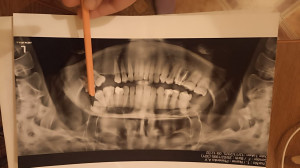

Добрый день! Была на консультации у врача-ортодонта, имеется перекрестный прикус. Доктор сказала удалить верхнюю семерку слева якобы она будет мешать при ношении брекет-системы, и освободит тем самым место для пятерки, которая вообще в небе оказалась из-за деформации прикуса. Хирург же говорит обратное - не стоит удалять этот зуб так как он не будет мешать брекетам,челюсть расширится. Подскажите. кто прав?

Здравствуйте. По снимку действительно видно скученность и перекрестный прикус. Удаление зуба проводится не всегда и это зависит от того, сколько места можно получить за счет расширения дуги и перемещения зубов. Если пятерка полностью прорезалась и есть шанс вывести ее без удаления, лучше сохранить семерку. Решение принимается после точных измерений по диагностическим моделям и компьютерной симуляции прикуса, поэтому целесообразно получить мнение ещё одного ортодонта, работающего с расширением дуги без удаления зубов.

Здравствуйте. По снимку видно, что пятерка действительно смещена в небо из-за нехватки места, но семерка выглядит функциональной и не разрушена. В вашей ситуации вероятнее всего можно создать пространство ортодонтически  за счёт расширения дуги и перемещения зубов. Поэтому удалять семерку пока нецелесообразно. Оптимально сделать 3D-диагностику (КЛКТ) и план лечения в цифровом виде, чтобы точно рассчитать, можно ли вывести пятерку без удаления.